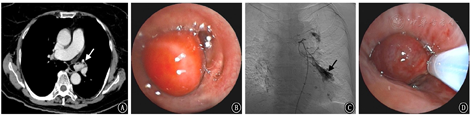

对于重症感染的患者,需反复行支气管镜灌洗治疗清除支气管内脓性分泌物,可有效防止感染扩散,解除气道阻塞,减少细菌对支气管的炎性损伤,且由于支气管扩张症患者存在潜在致病菌的定植,支气管镜检查还可留取气道内标本行病原学检查,明确病原菌,指导临床用药,减少耐药菌的产生。但支气管扩张症患者大多伴有支气管动脉或非支气管性体动脉扩张以及末梢血管床增生,极易合并危及生命的大咯血,行支气管镜检查及治疗存在一定风险,而血管介入为支气管镜的运用提供了保障。先行血管增强CT了解患者的体动脉情况,然后通过SAE栓塞异常血管,可起到即时止血的作用,之后再行支气管镜诊疗。这样,在能确保患者安全的情况下,进行气道介入治疗以达到预期的临床效果,即提高疗效,缩短住院时间,减少感染复发。病例2:男性患者,62岁,因"咳嗽、咳痰伴发热1周"入院,既往有支气管扩张症病史。联合治疗情况见图3。

若肿瘤侵犯至气道内或压迫气道导致阻塞,患者可出现严重呼吸困难,需紧急处理,通常处理方法有内镜下高频电治疗、氩气刀治疗、光动力治疗、冷冻治疗或支架置入术。但肿瘤性病变供血丰富,故气道介入治疗容易导致大咯血危及生命。可先行支气管动脉增强CT,观察瘤体供血血管是否丰富,寻找肿瘤供血责任血管,然后再行SAE,可降低肿瘤切除过程中出血的程度及风险。病例3:女性患者,72岁,因"间断咳嗽伴活动后喘气1月余"入院;患者有咳白痰,痰中偶带血丝,不能左侧卧位。联合治疗情况见图5。